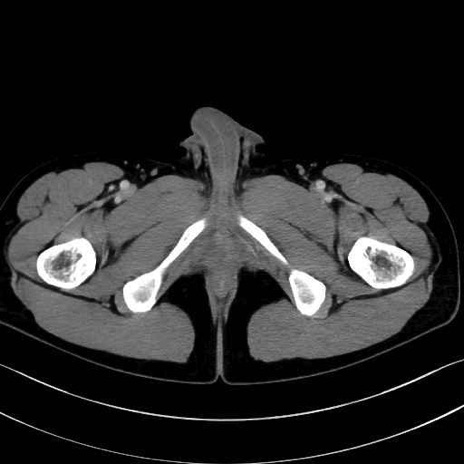

5. 大腿前面(大腿四頭筋群・伸筋群)

縫工筋 (Sartorius)

大腿直筋 (Rectus femoris)

外側広筋 (Vastus lateralis)

中間広筋 (Vastus intermedius)

6. 大腿内側(内転筋群)

恥骨筋 (Pectineus)